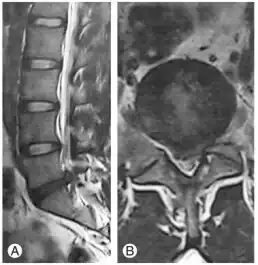

In symptomatic cases the diagnosis should be confirmed by an MRI scan. However, in cases with slight symptoms, a faster and cheaper CT scan (although it is inferior to MRI scan) may be recommended. While a CT scan can show the bony structures in more detail, an MRI scan can better portray soft tissue.

Diagnosis can be made on clinical basis with MRI findings